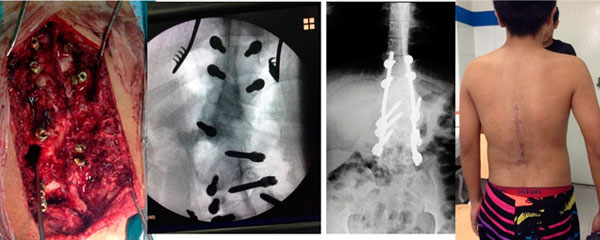

Me diagnosticaron escoliosis cuando tenía 13 años, en el año 2010 y ese mismo año me operaron en el mes de octubre. Al inicio, no me gustó la idea de la operación porque interfería con algunos planes que ya tenía en mente, pero sabía que si quería estar bien, tenía que sacrificarlos porque más importante era mi salud. No muchos doctores saben de esta enfermedad, gracias a Dios conocí al Dr. Cárdenas que fue muy amable y amigable conmigo y me explicó con todo detalle como sería la intervención; así que más que miedo, sentía emoción porque llegara el día.

Después de mi operación, solo estuve internada 4 días. Tengo 11 tornillos en mi columna y ya llevo 5 años de operada; vivo una vida normal y soy feliz.